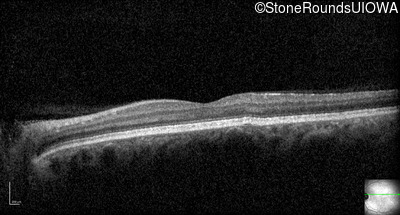

Optical Coherence Tomography - Left - 20/200

Exemplar / OCT Stack

OCT Stack